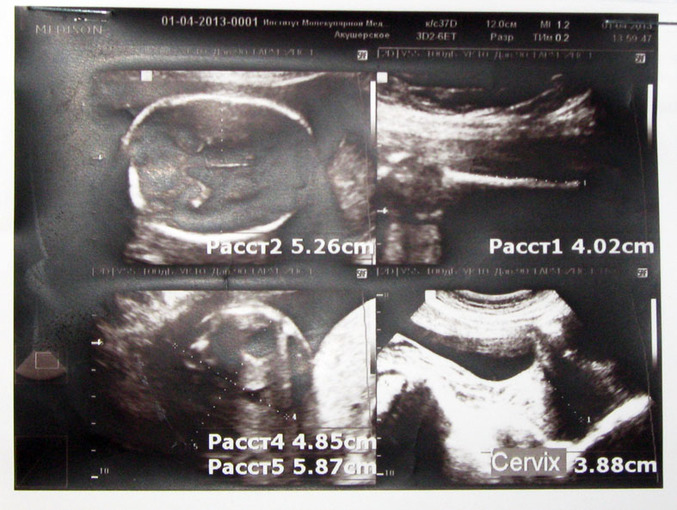

Вчера пошла на повторное УЗИ, проверить что с гипертонусом, к счастью его не оказалось, малышка в порядке, сердечко работает исключительно хорошо (132 удара в минуту), но!!! с 11 марта по 1 апреля малышка выросла всего на неделю, и узист ставит 21-22 недели... параметры:

БР Головы - 52, ДО Живота - 53, тазобедр. кость - 40, вес - 500 гр, рост соответствует 21-22 неделям...